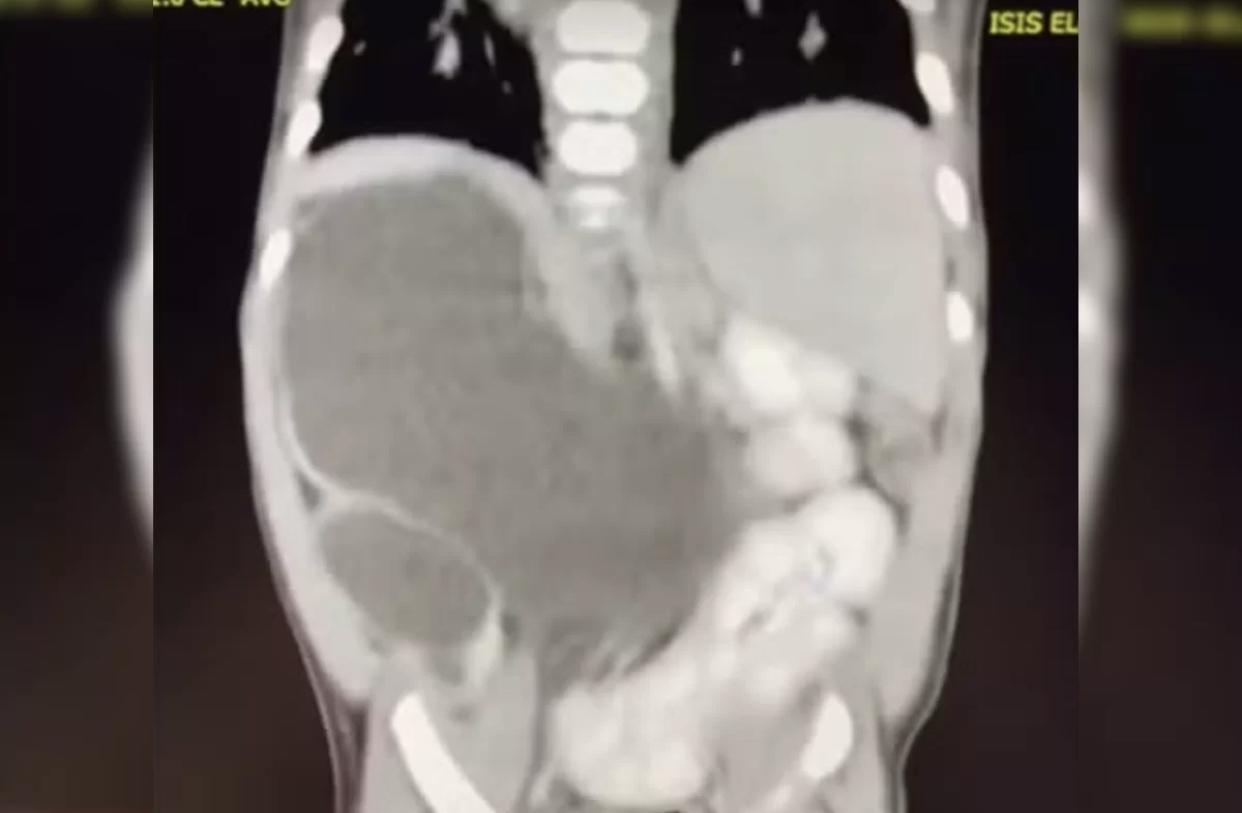

Incluída nos casos raríssimos da medicina, uma menina nasceu com quatro rins. Hoje com 1 ano e 1 mês, a pequena Isis Eloah Ferreira Alves está entre os cerca de 100 casos da medicina documentados na literatura mundial. O caso, publicado pelo G1, é é conhecido na medicina como “rins supranumerários” e demanda acompanhamento.

A mãe da menina, Thalia Silva Alves, de 21 anos, contou que Isis Eloah já precisou passar por diversas internações. Segundo ela, a filha nasceu prematura, tem alguns atrasos motores, mas leva uma vida normal. “Minha filha é rara e única”, disse a mãe.

A família mora em Formosa (GO), mas Isis nasceu no Hospital de Sobradinho, em Brasília. Por ser prematura, precisou ficar na incubadora. Na ocasião, os médicos não suspeitavam da condição de Isis. Ela foi transferida para o Hospital da Criança José Alencar (DF), onde foram descobertos os quatro rins.

Aos 5 meses, quando houve a necessidade de Isis passar por uma cirurgia, os médicos confirmaram que ela tinha nascido com quatro rins. Como Formosa fica a cerca de 80 quilômetros do Distrito Federal, a menina hoje é tratada no Hospital da Criança de Brasília (HCB).